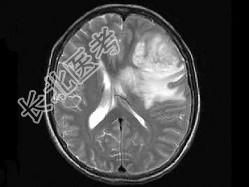

- 单项选择题女,52岁, 头痛伴呕吐2周,根据所提供图像, 最可能的诊断是 ( )

A、转移瘤

B、星形细胞瘤Ⅱ级

C、星形细胞瘤Ⅰ级

D、少枝胶质细胞瘤

E、脑脓肿